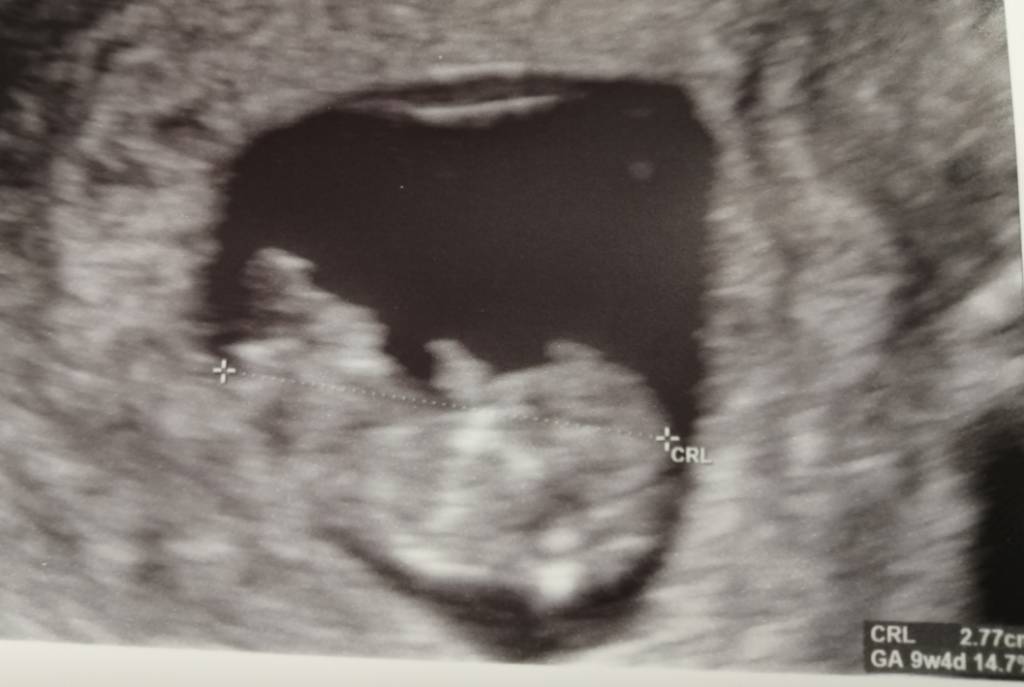

Z maluszkiem wszystko ok, rusza się i to jest najpiękniejsze, co w życiu widziałam [emoji7] już taki mały człowieczek, ma rączki, nóżki, no wszystko żeby wyglądać jak człowiek [emoji16] serduszko 178, lekarz mówił, że ok. No i ma już 2,8 cm [emoji3590] na zdjęciu tak korzystnie nie wypadło, ale na usg na żywo to jest boskie [emoji3059]

Następna wizyta 08.10, to będą prenatalne. Mam zrobić tydzień wcześniej pappa [emoji6]

Aha, no i jest teraz już 2 dni młodsza niż z om, więc po prostu będę liczyć z om i jutro zaczynam 11 tydzień [emoji3590]